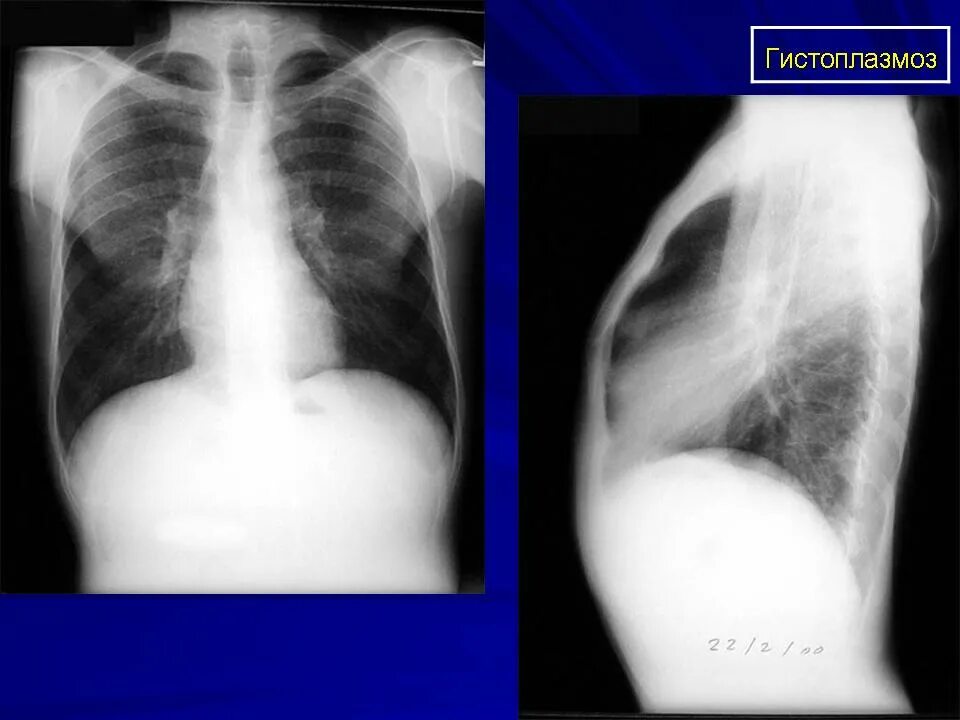

Гистоплазмоз это